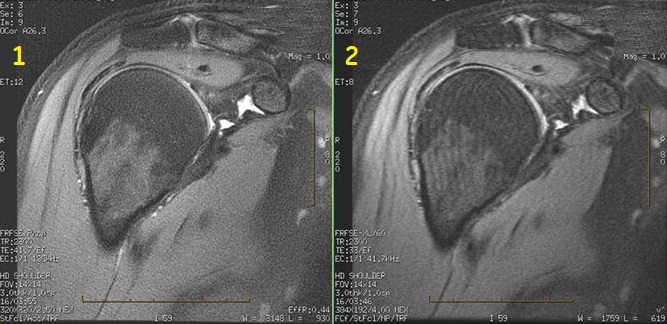

Musculoskeletal applications

Typically use PROPELLER to acquire PD, T1 and T2-contrast weighted shoulder, knee and wrist images. It is critical for optimum image quality to place the wrist above the head at magnet isocenter. Voluntary or involuntary (for example, breathing motion on shoulders) is minimized in comparison to FSE scans.

Figure 4. Motion reduction shoulder comparison

Table 4. Image legend

Number

Description

1

PROPELLER image

2

FSE image